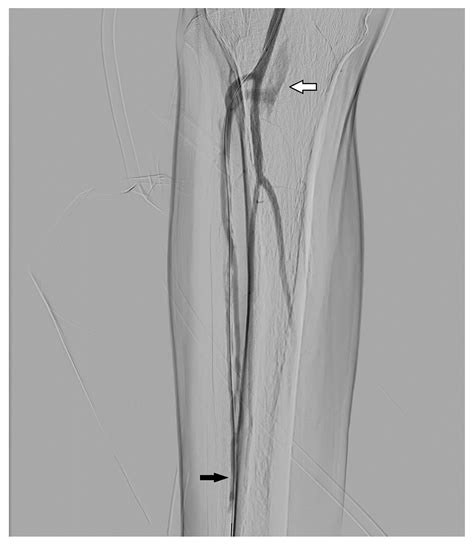

• Peripheral Vascular Disease: Assists in identifying blockages in the legs or abdomen that may require angioplasty or stent placement.

1. Preparation and Access: After local anesthesia is applied, a thin, flexible tube known as a catheter is inserted into a large blood vessel, usually the femoral artery in the groin or the radial artery in the wrist.

5. Intervention: If a blockage or abnormality is found, the physician may perform an intervention, such as balloon angioplasty or stent deployment, immediately during the same session.